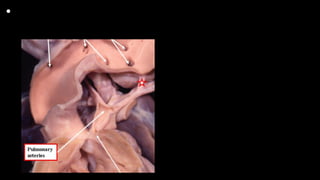

This specimen has tetralogy of Fallot with

pulmonary atresia. The pulmonary supply is

through multiple systemic-to-pulmonary

collateral arteries. The star shows the

connection between one of the collateral

arteries and the intrapericardial pulmonary

arteries. All the other arteries join with the

intrapericardial pulmonary arterial supply, or

else supply segments of the lung directly. The

task of the clinician is to display the supply of

the various collateral arteries and their

communications with the intrapericardial

pulmonary arteries.